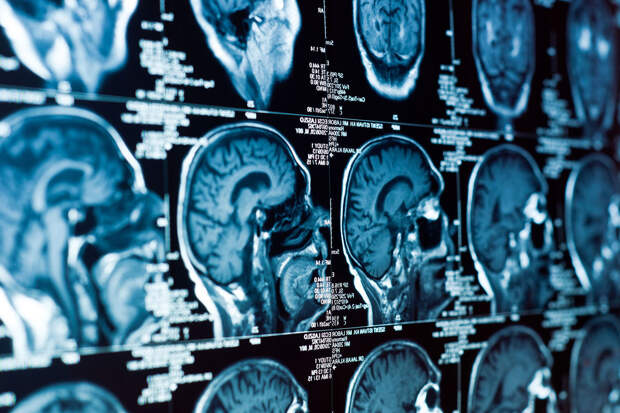

Ученые Университета здоровья Фудзита и Токийского столичного института медицинских наук установили, что "гиперзрелость" и ускоренное старение гиппокампа могут быть причиной тревожного расстройства. Работа опубликована в журнале Neuropsychopharmacology (NРР).

Гиппокамп — часть мозга, отвечающая за эмоции и память.

В норме его нейроны активно развиваются в раннем возрасте, после чего их активность постепенно снижается. Однако японские ученые обнаружили, что при некоторых психических расстройствах этот процесс идет слишком быстро: клетки созревают и стареют раньше времени.Авторы проанализировали 17 генетических наборов данных мышей с различными нервно-психическими нарушениями — тревожностью, депрессией, шизофренией и нейродегенерацией. Они нашли специфические "подписи" активности генов, указывающие на ускоренное развитие и старение гиппокампа. Такой тип они обозначили как "гиперзрелые модели".